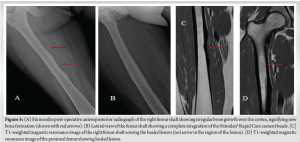

With the working diagnosis of osteomyelitis in mind, Cierny-Mader Pennick classification (9) type III A (localized osteomyelitis in a host with normal immune system) and considering the symptomatic status of the patient with persistently high CRP and ESR values, she was planned for open biopsy and debridement of the osteomyelitis. Under spinal anesthesia, aseptic precautions, the patient was positioned supine with leg in figure of four position, direct medial approach to the osteomyelitis lesion, and the lesion was exposed. The mid-shaft of femur showed periosteal reaction with necrotic tissue around the bone (Fig. 3). Thorough debridement of the periosteum and sub-periosteal tissue was done. Drill holes were made into the femoral cortex to look for intramedullary pus. No active pus was drained. Thorough wash was given and debridement done until bleeding bone and healthy tissues were seen. Antibiotic impregnated beads (vancomycin and gentamycin) (Stimulan® Rapid Cure, Biocomposites, UK) were placed in the bone. Adequate hemostasis was achieved. Wound was closed in layers.

The tissue samples were sent for histopathological examination, culture and sensitivity, and X-PERT analysis for tuberculosis. The culture grew Salmonella spp. Sensitivity pattern showed the organism to be resistant to amikacin, ciprofloxacin, gentamycin, levofloxacin, and cefaperazone-sulbactam. It was sensitive to ofloxacin, ceftriaxone, amoxicillin- clavulanic acid, and ertapenem. The X-PERT analysis was negative for tuberculous bacilli. Species identification of the bacillus could not be done. The histopathological examination showed acute inflammatory exudate with necrotic tissue, consistent with features of osteomyelitis of femur. Postoperatively, we ruled out sickle cell disease by a peripheral smear. She was started on intravenous ertapenem based on the MIC level and continued for 6 weeks, followed by 2 weeks of oral cotrimoxazole. Only partial weight-bearing with support was allowed till 6 weeks postoperatively, full-weight-bearing thereafter. She presented for follow-up on day 7, 14, 6 weeks, 3 months, 6 months, and 1 year postoperatively. Serial CRP level monitoring was done. Follow-up radiograph showed healing of the cortex and integration of the antibiotic beads (Fig. 4 and 5). Repeat MRI was done at 6-month mark postoperatively which showed healed lesions at both mid shaft of femur and proximal tibia (Fig. 6). The patient is currently asymptomatic and doing all activities of daily living.